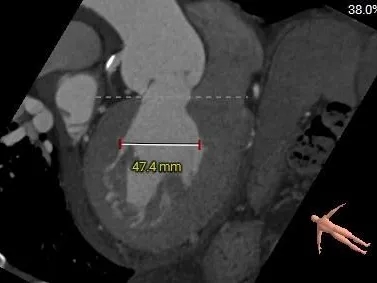

术前CT分析

-

单纯反流三叶式主动脉瓣,瓣叶稍厚,右冠瓣脱垂;

瓣环径约为26.4mm,流出道偏直筒型;

左冠开口高度约为25.2mm,右冠开口高度约为23.2mm;

瓣环水平夹角59°,横位心临界值,升主动脉明显扩张;

外周入路走形略迂曲,左右股动脉直径偏细,主动脉弓部至双侧下肢血管可见明显钙化分布;

左侧下肢动脉入路最小平均内径5.4mm,右侧下肢动脉入路最小平均内径6.2mm,右侧穿刺点附近存在连续性钙化。

主动脉根部测量

Annulus:26.4mm

LVOT:26mm

VR图

SOV:

45.8*45*41.3mm

STJ:

41.3mm

AAO:

43.3mm